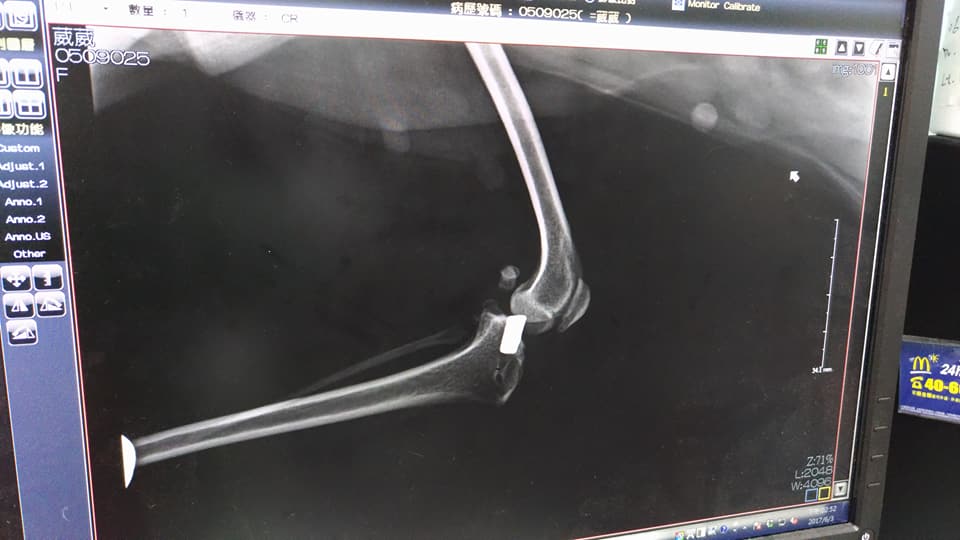

【第二次開刀後的復健即回診-右後腳】

8/19 沐恩 葳葳開刀出院

葳葳右腳手術結束,復健方式同左腳,一日三次

8/25 沐恩 葳葳回診拆線

右腳傷口復原良好,但他不敢用右腳,所以要加強復健,早晚各一次,時間允許下午一次